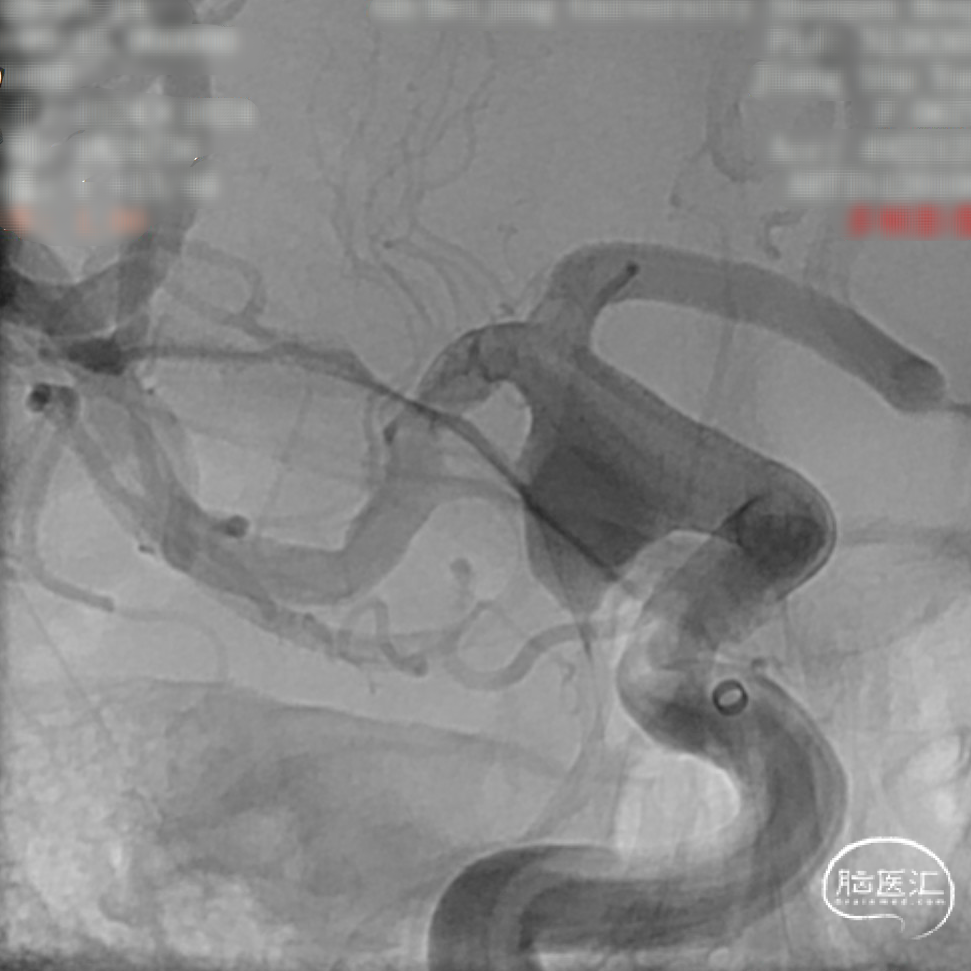

DSA造影:

工作角度:

微导管到位后释放支架头端。

头端完全打开,锚定。

完全覆盖动脉瘤颈后拟过弯。

支架完全释放。

造影明确打开贴壁满意。

正侧位造影:支架放置后可见动脉瘤内造影剂明显滞留。